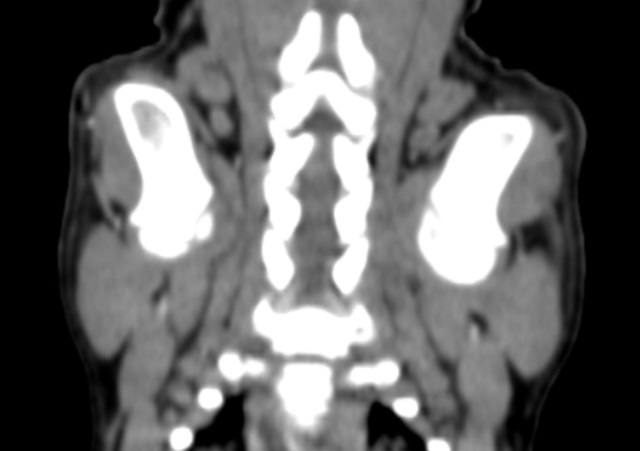

Была проведена повторная КТ с внутривенным контрастированием, по результатам которой было выявлено значительное увеличение размеров капсул в обоих плечевых (рис. 3, 4), локтевых и тазобедренных суставах, а также в левом коленном суставе по сравнению с данными первоначального КТ-исследования.

На основании клинических симптомов, анамнеза приема левофлоксацина, отсутствия ортопедических симптомов до поступления пациента в клинику, результатов анализов крови и синовиальной жидкости, а также проведенной КТ был поставлен диагноз «множественная артропатия, вызванная применением фторхинолонов».